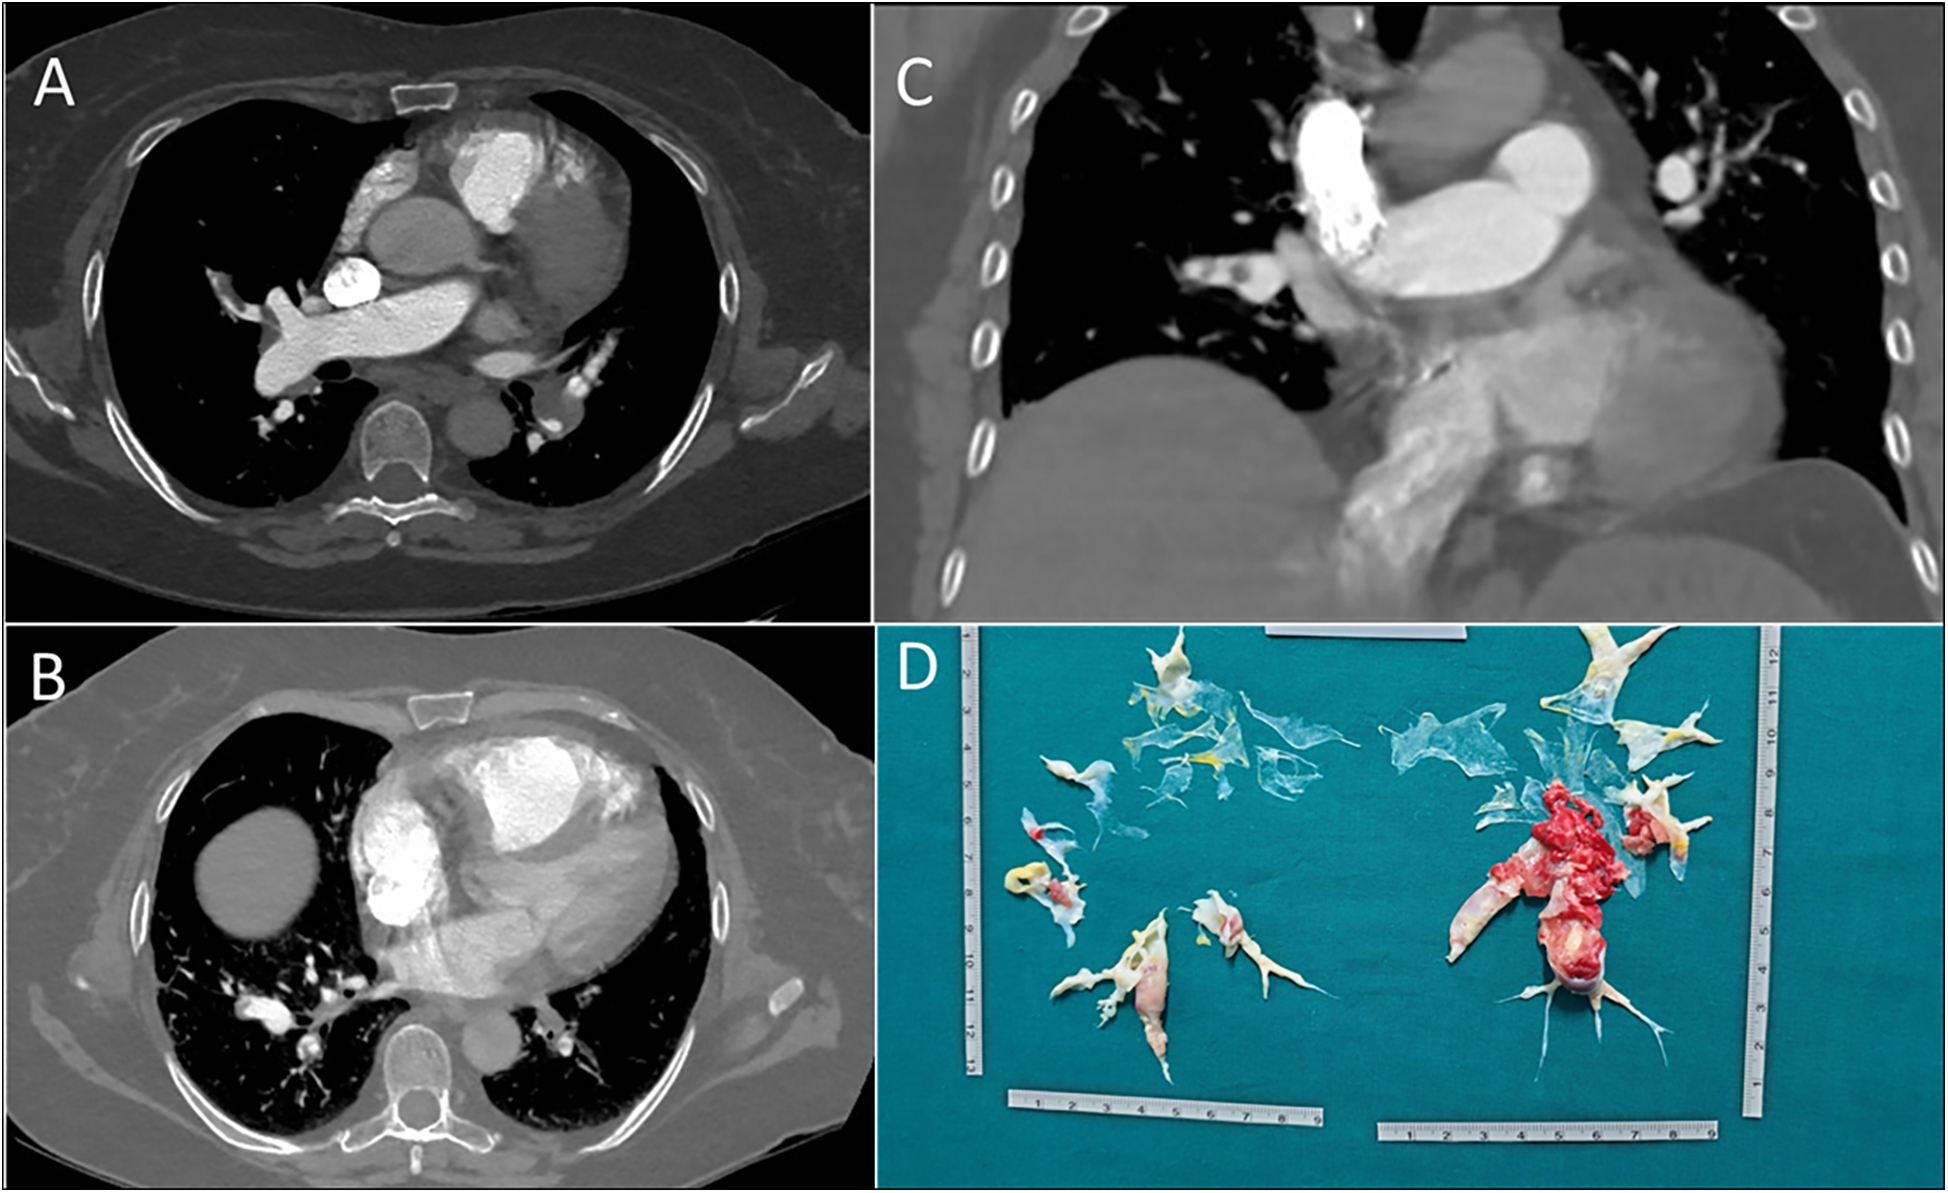

Figure 4

(A) axial scansion of chest CT with contrast. It shows a filling defect of a thrombo-embolic nature in the branch of the right pulmonary artery tributary to the middle lobe. (B) Axial scansion of chest CT with contrast. A filling defect of thrombo-embolic nature in the right and left pulmonary artery branches tributary to the lower lobes can be observed. (C) Coronal scansion of chest CT with contrast. It shows a filling defect of a thrombo-embolic nature in the branch of the right pulmonary artery tributary to the middle lobe. (D) Postoperative surgical finding of pulmonary thromboendarterectomy.

Axial computed tomography showed partial occlusion of pulmonary arteries, consistent with CTEPH (Figures 4A–C). The diagnosis was confirmed by a V/Q scan showing mismatch and by RHC, which revealed pre-capillary pulmonary hypertension and a severe reduction in CI (mPAP 54 mmHg, PAWP 10 mmHg, PVR 14 WU, CI 1.8 L/min/m2). Histological analysis of the thrombus revealed that it had undergone a process of reorganization over time, leading to the formation of a thrombus composed of platelets, fibrin, and collagen.

During the thrombophilia test, a partial reduction in protein C was observed. However, since the decrease was limited, it is not regarded as clinically significant. Corticosteroid therapy was initiated to address the progressive reduction in platelet count (to 25 k/μl), and vitamin K antagonists were started for anticoagulation. The patient was referred to the PTE (Figure 4D). The surgical procedure was performed successfully; however, the patient unfortunately died during the postoperative period due to an infection.